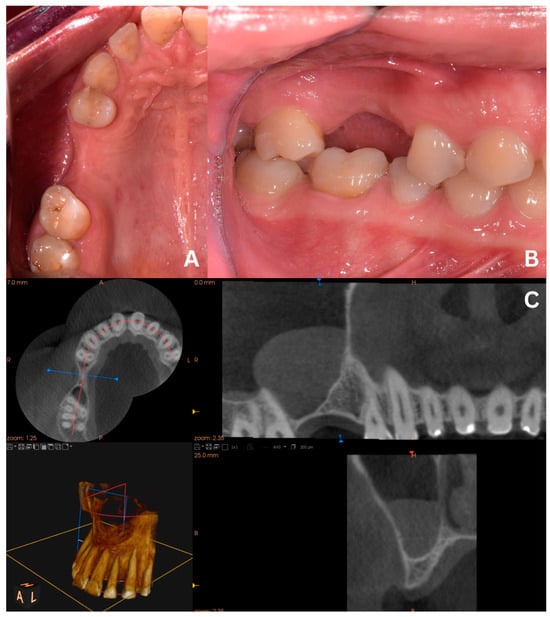

The process of removing the cyst’s lining poses a threat to the excessive widening of the Scheiderian membrane’s perforation. Generally, this type of complication requires enlarging the osteotomy window in order to avoid further perforation widening during membrane elevation. However, in certain cases, i.e., when teeth roots restrict the maximum size of the osteotomy window, shredding the Schneiderian membrane and progressing perforation is highly undesirable. Such difficulties may be restrained with a slight modification of the primary version of the CET, as presented in the second case, where only tooth 16 was missing (Figure 8).

2.2. Case 2—Final Version

After elevating the mucoperiosteal flap (Figure 9A), a minor, about 3–5 mm wide osteotomy window is opened simply to allow biopsy (Figure 9B) and remove the cyst’s lining (Figure 9C,D). The perforation will not exceed the size of the minor window as the Schneiderian membrane remains safely attached to the bone. Afterward, a second, major osteotomy window is made around the minor one (Figure 10A). The existing perforation should be located in the center of the major window. Then, the bone ring is gently elevated and detached from the Schneiderian membrane (Figure 10B,C). Elevation should start from the center of the ring, not from its margin, since if the new perforation appears on the sidelines, it will be almost impossible to manage properly. From this point, the whole procedure is similar to the one described above: elevating the Schneiderian membrane, managing its perforation, and completing the augmentation.

Figure 8. Croco Eye Technique—final version. Screenshot of the pre-op CBCT scans with a visible radiopaque lesion in the right maxillary sinus, insufficient alveolar ridge height, and noncontinuous bone of the sinus floor due to past oroantral communication (OAC) (red arrow).